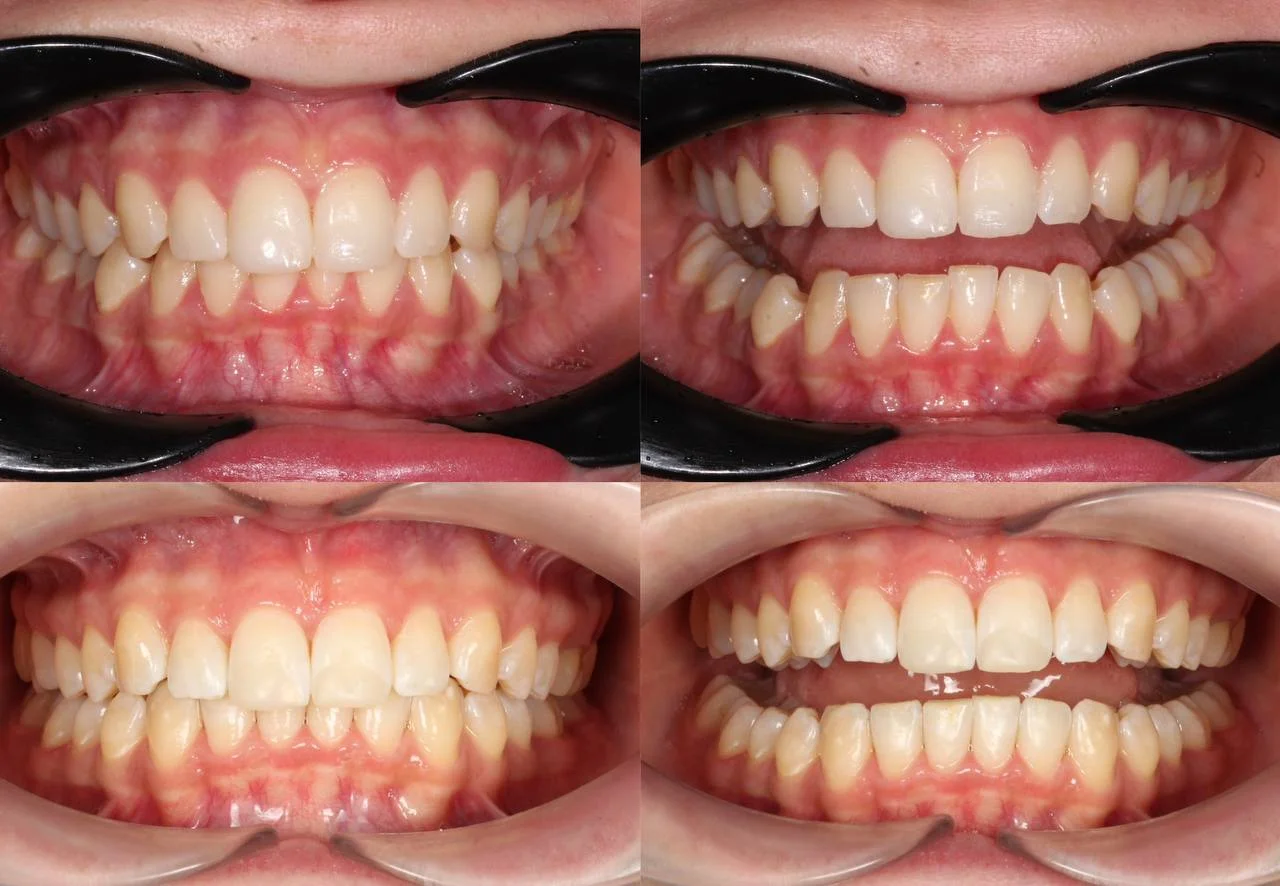

Зубы выровнены, скученность устранена, линия смыкания нормализована. Установлены несъёмные ретейнеры на обе челюсти, сняты слепки для ретенционных кап.

Решение: Поставили элайнеры Click на обе челюсти. Начали с 32 кап, но случай потребовал три дозаказа: 30, 10 и 10 кап — итого 82 капы за 30 месяцев. Количество дозаказов объясняется и сложностью случая (скученность плюс деформация кривой Шпее), и тем, что контрольные визиты были реже обычного из-за проживания за границей. Тем не менее результат достигнут: зубы ровные, смыкание в норме. На ретенцию пациентка приехала отдельно — зафиксировали ретейнеры на обе челюсти, сняли слепки для ретенционных кап.

Сложный случай: скученность на обеих челюстях плюс деформация кривой Шпее — жевательные зубы на разной высоте. Дополнительный вызов — пациентка живёт за рубежом, визиты реже, контроль сложнее. Три дозаказа — много, но каждый был обоснован: основной набор расширил дуги и убрал основную скученность, дозаказы последовательно довели смыкание до нормы. 82 капы за 30 месяцев — результат получен.